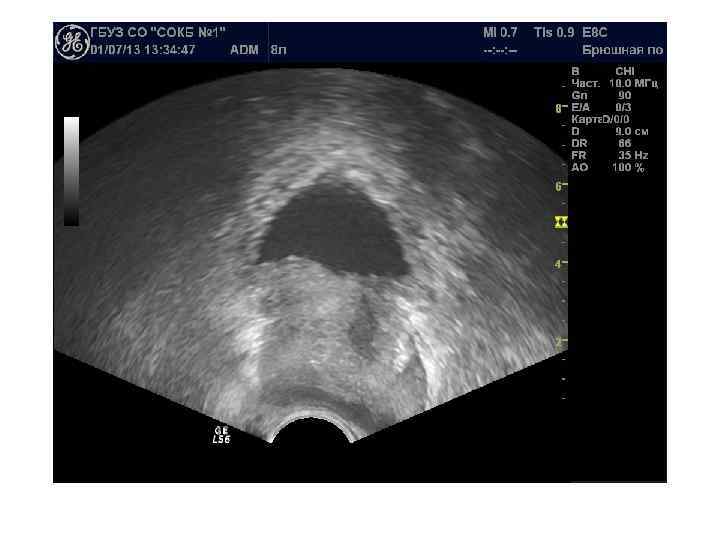

Доступы: трансабдоминальный, трансперинеальный, трансректальный, трансуретральный Трансабдоминальное исследование производится с помощью датчиков 3, 5— 5, 0 МГц и требует наполнения мочевого пузыря. При трансабдоминальном исследовании можно определить размеры и объем предстательной железы, выявить изменения, характерные для ДГПЖ, и определить особенности роста аденоматозных узлов. Не используется для выявления рака простаты. Трансперинеальное (чреспромежностное) исследование простаты: датчик 3, 5— 5, 0 МГц устанавливается на промежность. Исследование проводится при невозможности выполнения трансабдоминального или трансректального исследований. Качество визуализации не лучше чем при трансабдоминальном

Для трансректального исследования (ТРУЗИ) простаты необходим полостной трансректальный датчик 7, 5— 10, 0 МГц. При ТРУЗИ возможно точное определение размеров и объема железы, выявление тонких структурных изменений и особенностей кровоснабжения паренхимы. Исследование позволяет детально оценить состояние железы при ДГПЖ, особенности роста аденоматозных узлов, состояние паренхимы и капсулы. Трансуретральное исследование простаты не имеет существенных преимуществ перед трансректальным при значительно более инвазивной технологии.